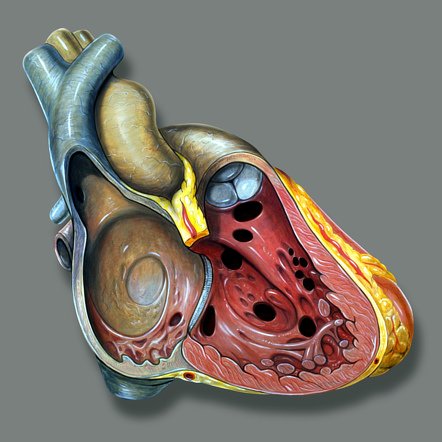

Preste atenção às fontanelas e ao fundo de olho da criança: fontanelas tensas ou quaisquer anormalidades no exame de fundo do olho são extremamente significativas. O abuso infantil nessa situação tem maior probabilidade de ter sido na forma de sacudir violentamente o bebê. Nessa situação, o movimento de chicote da cabeça da criança pode causar ruptura das veias corticais em ponte, que ligam as veias da dura e aracnoide, levando à formação de um hematoma subdural. Estes podem ocorrer bilateralmente, com uma freqüência 5 a 10 vezes maior que o sangramento epidural.

Os hematomas subdurais podem ocorrer de forma crônica em crianças pequenas que sofrem maus tratos, estando associados a fraturas cranianas em 30% dos casos. Hemorragias retinianas são encontradas em 75% dos pacientes com hematomas subdurais. Os exames neurológicos de imagem classicamente revelam lesões em forma de meia-lua entre o cérebro e o crânio.